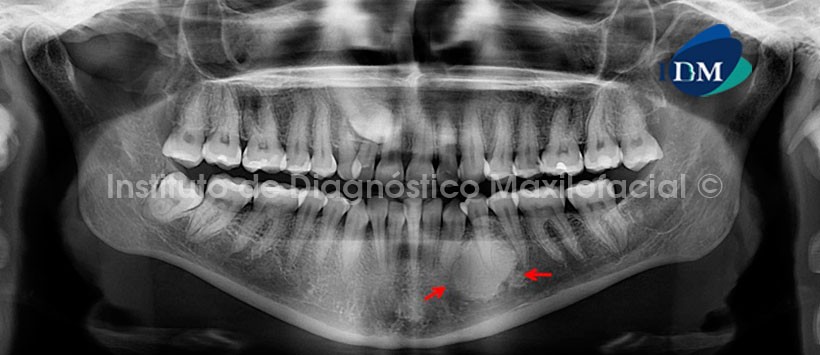

Estas son lesiones asintomáticas y son consideradas hallazgos radiográficos, pueden ser de varios tamaños desde 2mm hasta 2cm de diámetro, o las lesiones pueden ser tan grandes que cubren casi la totalidad del espesor de la mandíbula, pero no alcanzan un tamaño suficiente para causar expansión de las tablas óseas. En casos excepcionales se han reportado islas de hueso denso “gigantes” que miden hasta 7cm. Suelen ser de límites definidos y tener una forma redonda, elíptica, ovalada o irregular. La presencia de un halo radiolúcido o cápsula es raro. La periferie es usualmente bien definida pero ocasionalmente se entremezcla con las trabéculas del hueso circundante, con espículas que se irradian desde sus márgenes. Su apariencia interna puede ser uniformemente radiopaca, vidrio esmerilado, aspecto punteado o trabéculas gruesas que pueden extenderse más allá de la zona de mayor densidad. Pueden ser únicas o múltiples en un mismo hueso, o múltiples en diferentes huesos. Pueden ubicarse próximo a un diente sano, en los ápices de las raíces, entre las raíces o separada y lejos de los dientes.

La Osteoesclerosis Idiopática se presenta dentro del espesor del hueso medular, se puede extender desde la cima de la cresta del proceso dentoalveolar hasta la basal mandibular, pero no desplaza ni deforma corticales anatómicas. El espacio del ligamento periodontal puede estar obliterado por la masa o ser de espesor normal o ensanchado, característica que no ha sido explicada adecuadamente. La lámina dura de las piezas adyacentes a la Osteoesclerosis puede desaparecer y mimetizarse dentro de la masa esclerótica, la cual puede extenderse más allá de los ápices del diente adyacente y ocupar incluso el espacio interradicular en ambos sitios de un diente. En ciertos casos la Osteoesclerosis puede provocar reabsorción radicular externa, aunque es infrecuente. Tienen predilección por la zona de molares y premolares inferiores.